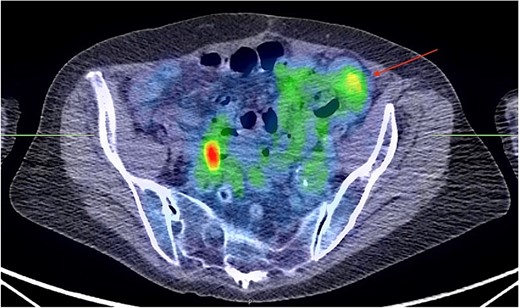

Image-guided needle biopsy of the pelvic mass was attempted; however, at the time of the procedure, the mass mobility made it impossible. Due to suspicion of potential involvement of the colonic wall, a colonoscopy was performed, which was unremarkable. A positron emission tomography scan confirmed the CT findings, exhibiting a rounded mesenteric nodule in the left quadrant measuring 2.6 cm, with elevated Fludeoxyglucose F18 (FDG) tracer uptake (Fig. 3).

PET scan showing a rounded nodule within the anterior mesentery in the left pelvis measuring 2.6 × 2.6 cm in size. It has a moderate tracer uptake with peak SUV of 3.6. (arrow). No other mesenteric nodules are identified. The image visualized on the right pelvis was considered a normal physiologic uptake within the bowel.